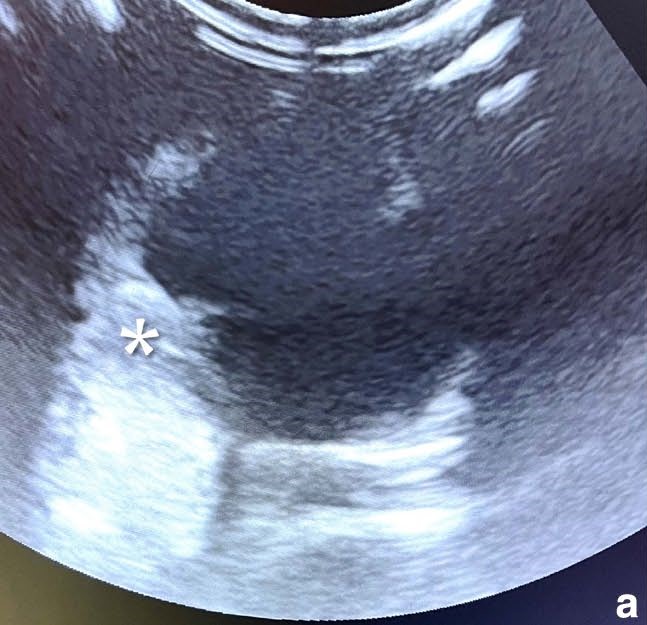

双眼角膜荧光素染色阴性。眼压:左眼20 mmHg,右眼90 mmHg。右眼超声显示虹膜与睫状体后方有一大而回声强的“肿块”(图2a),玻璃体腔无明显改变,无视网膜脱离。

图2. 超声图像:(a) 右眼,显示一个增大的高回声肿块(白色星号),从虹膜延伸至晶状体后囊。

右后肢肿胀处超声示股四头肌增厚、回声增强并周围水肿(图2bc)。肌内穿刺细胞学符合大细胞、高级别淋巴瘤。腹部超声示脾、胰腺增大,但脾穿刺未见恶性证据。

图2. (b) 右侧股四头肌,肌肉增厚且回声增强,周围伴水肿,肌筋膜界限不清;(c) 右侧腘淋巴结,大小和形态正常,但周围可见少量游离液体(白色箭头)。注意水肿已延伸至大腿后侧肌肉(白色星号)。